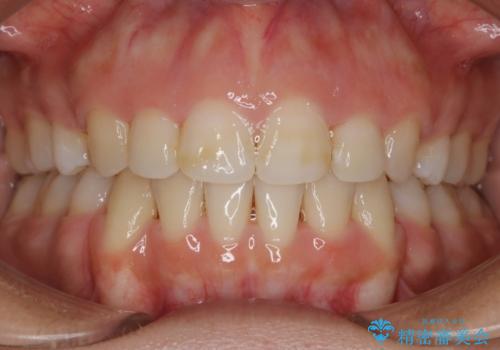

- 口元を下げたいという主訴でご来院されました。

ガタつきの度合いは軽度でしたが歯列の幅が狭く、その分前歯が上下とも前方に出てしまっていました。

しっかりと口元・顔貌まで変化を起こせるように上下左右の第一小臼歯を抜歯し、ワイヤー装置にて矯正を開始することとなりました。